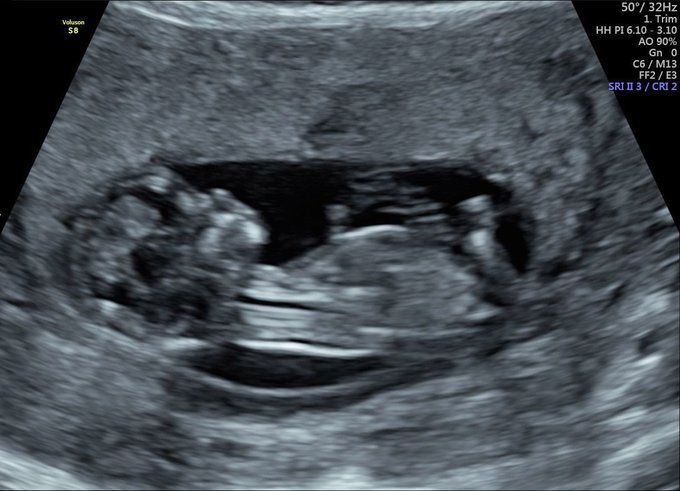

An early pregnancy scan offers reassurance in the early stages of pregnancy. You can have an early reassurance scan between 7 to 10 weeks into the gestation period, providing comfort and reassurance at this crucial and exciting time.